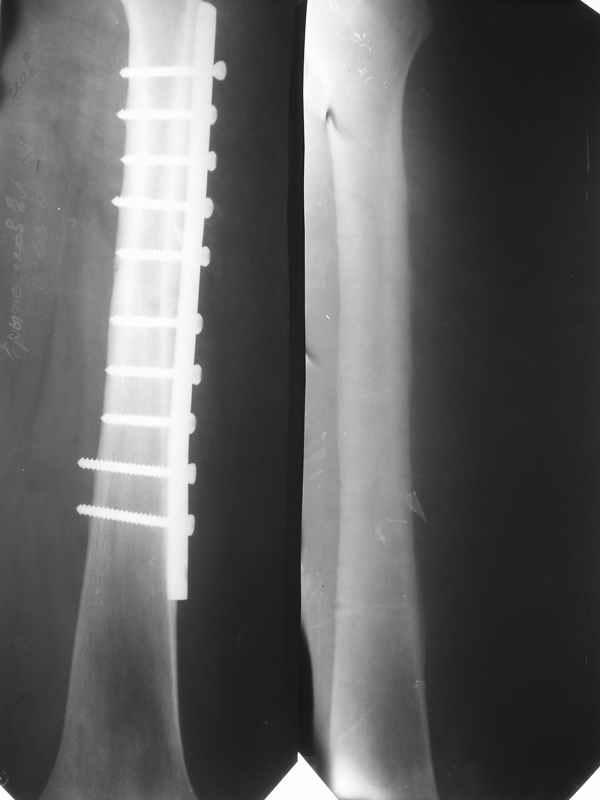

Здравствуйте. К нам поступил мальчик 15 лет с застарелым 7-месячным вывихом бедра из области. Травма мотоциклетная, при поступлении в больницу по месту жительства диагностирован перелом диафиза бедра и не распознан вывих бедра с этой же стороны.

Бедро было синтезировано пластиной и успешно срослось. Как поступить сейчас с вывихом? По КТ видны интерпонированные отломки, впечатление что это фрагменты головки бедра. Поделитесь, пожалуста, опытом. Спасибо.